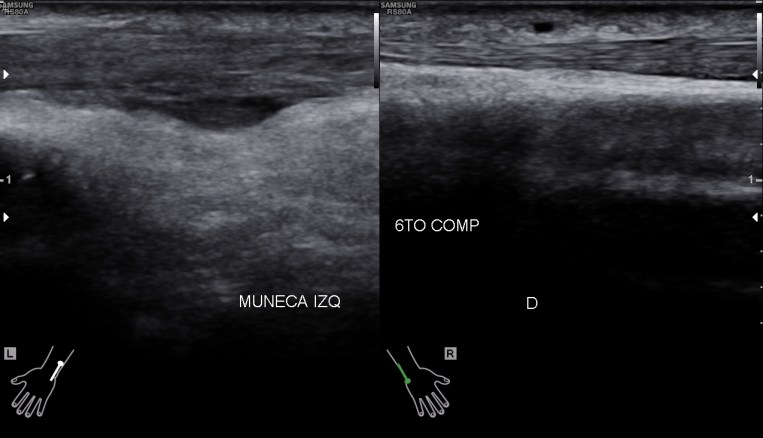

Situada en la corredera bicipital, vas a ver el bíceps como una estructura hiperecogénica, redondeada situado en el valle de la corredera. Observa como la imagen superior indica ausencia de líquido y normalidad y la inferior relación entre la anatomía y la patología donde el líquido rodea el tendón en relación con una posible tenosinovitis.